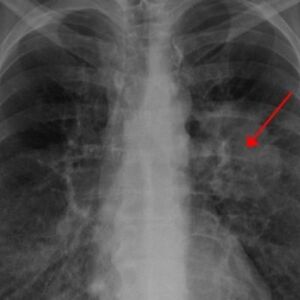

- Posebno treba da se paze oni s kardiovaskularnim problemima i astmatičari, kao i psihijatrijski pacijenti. Obavezno da uzimaju svoju terapiju, sve prepisane lekove i da redovno proveravaju pritisak. Često se javljaju u ovim periodima, guše se, skače im pritisak, pada im pritisak, razdražljivi su... Dešava im se sve ono čemu su inače skloni - objašnjava dr Milosavljević.